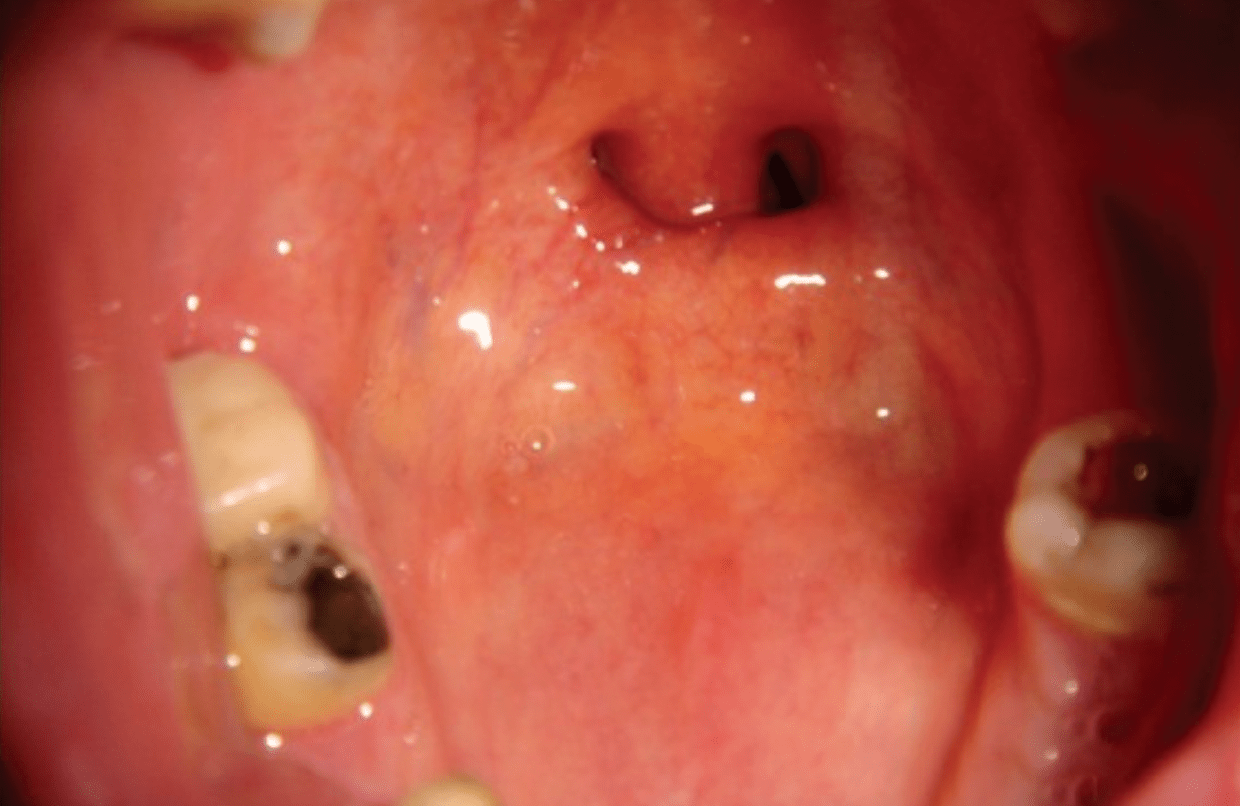

After his 2002 car accident, Kanye’s jaw was wired shut due to a comminuted mandibular fracture, a procedure known as intermaxillary fixation, which immobilizes the mandible by anchoring it to the maxilla so the bones can heal properly. If the fracture extended near the mental foramen and caused numbness of the lower lip and chin, the mental nerve was likely affected. Before giving rise to this nerve, the parent branch enters the mandible through a foramen located on which part of the bone?

Answer: Ramus of the mandible